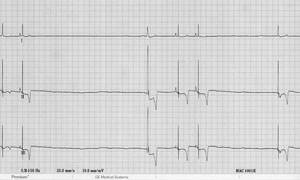

- Аритмии – слишком быстрое или слишком медленное сердцебиение (желудочковая тахикардия,

атрио-вентрикулярная блокада). Проблема характерна для дилатационной кардиомиопатии боксеров и доберманов, когда очень быстрое сердцебиение может привести к гибели собаки.Вест-хайленд-уайт терьры, миниатюрные шнауцеры предрасположены к синдрому слабости синусового узла. - Низкий венозный возврат (кровотечение, низкое давление в грудной клетке, повышение тонуса вагального нерва).

Особенно опасны приступы, сопровождающие нарушения сердечного ритма (слишком быстрое, или слишком медленное сердцебиение).